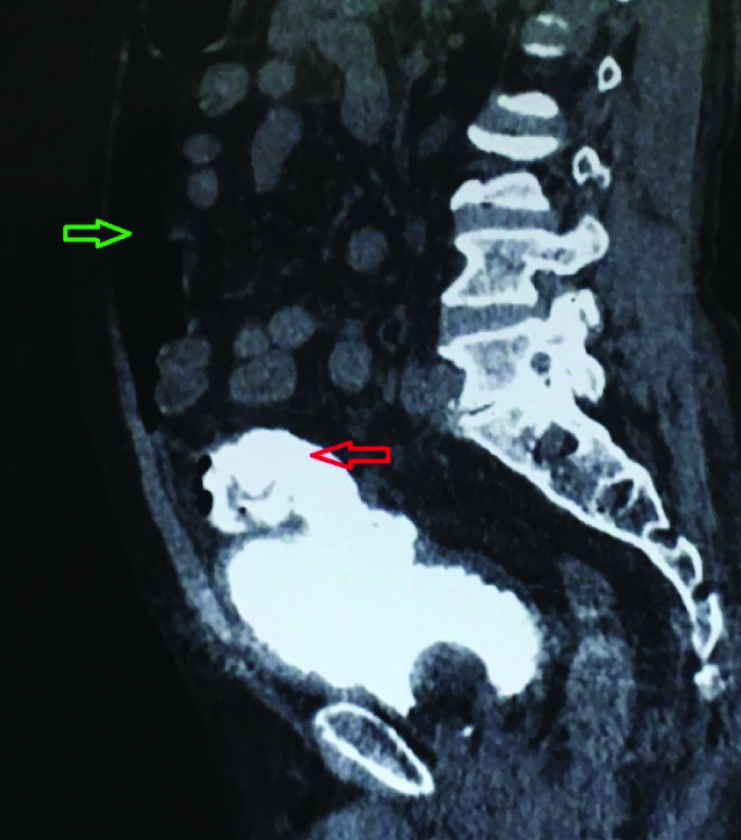

CT showing bladder perforation (red arrow) and urinary ascites (green arrow).

Patient was referred to us, on his second postoperative day. On examination, abdomen was soft, non distended and non tender, vitals were stable. Drain fluid creatinine was measured and found to be 56 mg/dL. Simultaneous serum creatinine was 1.5 mg/dL. Contrast “enhanced” CT scan was done which revealed intraperitoneal bladder perforation, pneumoperitoneum and a cysto-enteric fistula with contrast going into the small intestine [Table/Fig-1,2,3 and 4]. Though, it was an intraperitoneal bladder rupture with a cysto-enteric fistula a conservative management was planned, as there were no abdominal signs with stable vitals. In further course, patient developed a left lumbar lump containing purulent material, which was drained subsequently.